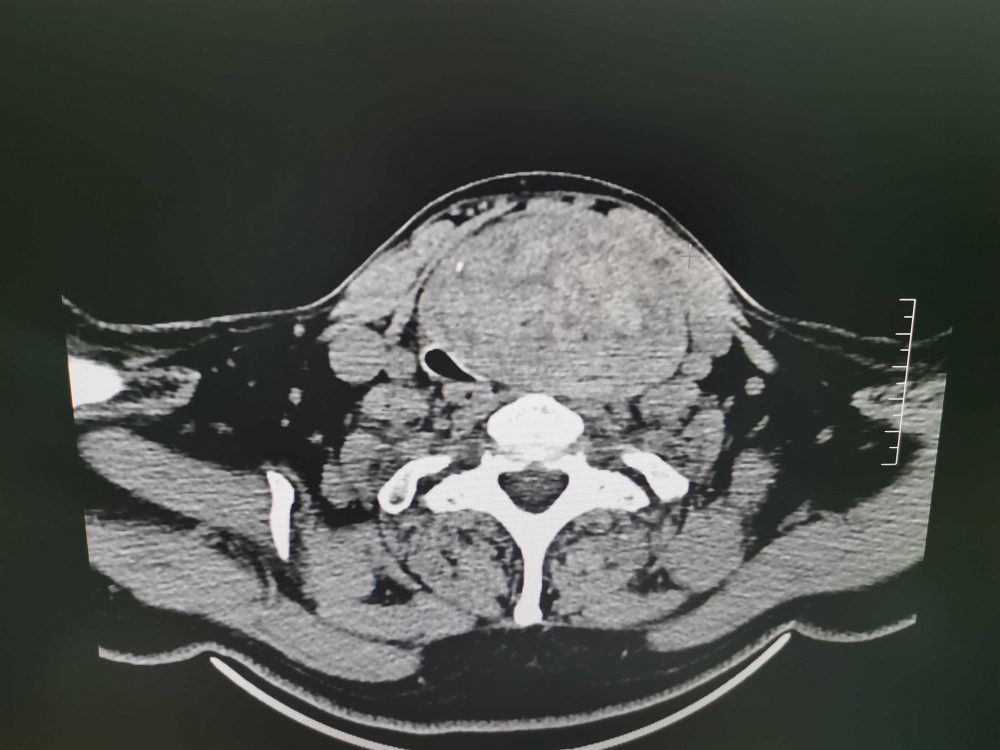

患者郭×芹,57歲,多年來(lái)一直承受著腫瘤壓迫氣管所帶來(lái)的痛苦與不便。在活動(dòng)、工作時(shí)總感覺(jué)呼吸不暢,甚至出現(xiàn)呼吸困難;嚴(yán)重時(shí),必須放下手里的工作休息好久方能有所緩解,且長(zhǎng)期口服治療甲亢的藥物?;颊哂?月11入住普外二科,該科團(tuán)隊(duì)為其全力以赴。術(shù)前聯(lián)系麻醉、重癥醫(yī)學(xué)、內(nèi)分泌、影像等多個(gè)學(xué)科會(huì)診協(xié)助治療,做好圍手術(shù)期充分準(zhǔn)備,并精心制定了手術(shù)方案。術(shù)中準(zhǔn)確地鑒別了巨大甲狀腺腫瘤的位置(有近三分之一的瘤體位于胸骨下)。為了能夠保證手術(shù)順利安全,手術(shù)過(guò)程中確保了并發(fā)癥的最低風(fēng)險(xiǎn),并通過(guò)現(xiàn)代化的技術(shù)和設(shè)備保護(hù)周圍的重要器官,順利完整切除了腫瘤,腫瘤約8×6×5cm。術(shù)后,給予全面的康復(fù)指導(dǎo)和關(guān)懷,并鼓勵(lì)患者用堅(jiān)韌的意志和積極的態(tài)度配合治療,在短時(shí)間內(nèi)取得了顯著康復(fù)效果。